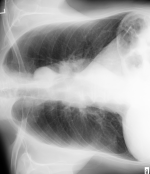

原始图像